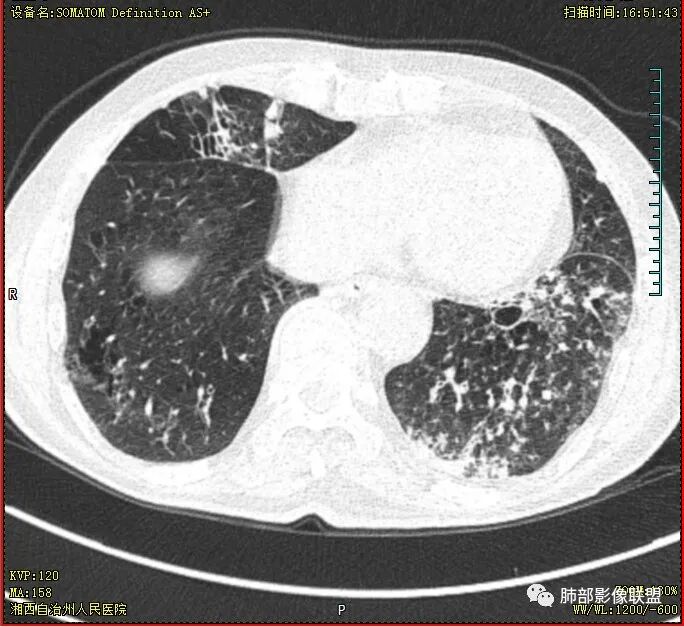

老年慢性长期吸烟,痰中带血伴发高热。左下肺大片不均质实变里可见一含气液平厚壁空洞,内壁有坏死物残留,增强可空洞壁明显强化轮廓显示清晰,空洞位于肺门侧,近端支气管壁不规则增厚。两肺散在斑片状影,并见小树芽。18号复查肺窗空洞显示不清,20号用了俯卧位扫描,液体向下流动空洞又显示出来了。左下肺病灶有变小,还是考虑感染性病变,结核合并感染,鉴别鳞癌。

双肺多发结节影,树芽征,小叶中心分布,左肺下叶不规则空洞,洞内壁光滑,见液平,洞壁似与支气管相通,增强扫描明显强化,可见血管造影征。三周左右复查空洞明显缩小。

18号复查肺窗空洞显示不清,20号用了俯卧位扫描,液体向下流动空洞又显示出来了。

胸部CT:双肺多发小斑片、树芽、索条灶,左下肺大片不均质实变,远肺门侧厚壁空洞,气液平,内壁有坏死物残留,增强可空洞壁不均匀强化,近端支气管壁不规则增厚堵塞,实变影内可见与洞壁平行支气管。抗炎3周有缩小。

当时就觉得这个强化像个肿瘤,但时复查洞明确变小了,就考虑感染了,不过没想到是腺癌

大雄: 空洞短期变化,这个确实有迷惑性,也遇到过几例,这个病例应该是合并感染了

3.注意到左肺下叶空洞性病灶,腔壁厚度不均,环形强化较为明显,壁间支气管血管影走行,腔内液气平面,这通常见于感染性病灶,如脓肿,经治疗病灶吸收也高度支持病灶主体成分为脓肿。

尽管坏死明显,但穿行血管结构自然,血供如此丰富,鳞癌的判断使人望而却步,腺癌的判断也缺乏有说服力的线索。